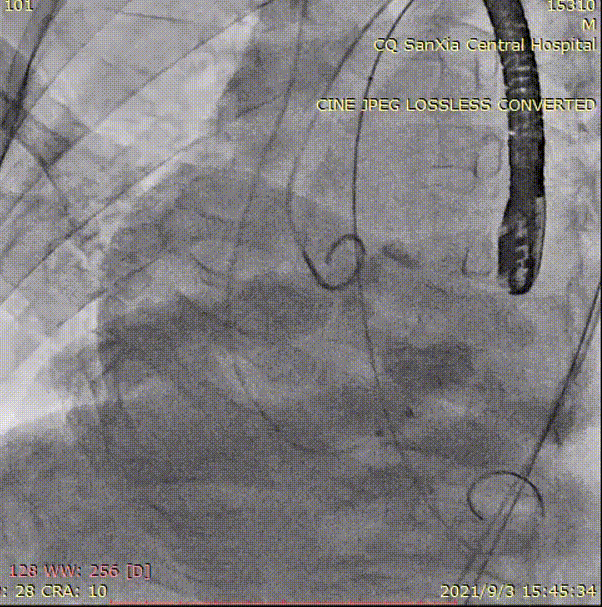

根部造影

Numed18mm球囊预扩,左右冠脉都有显影